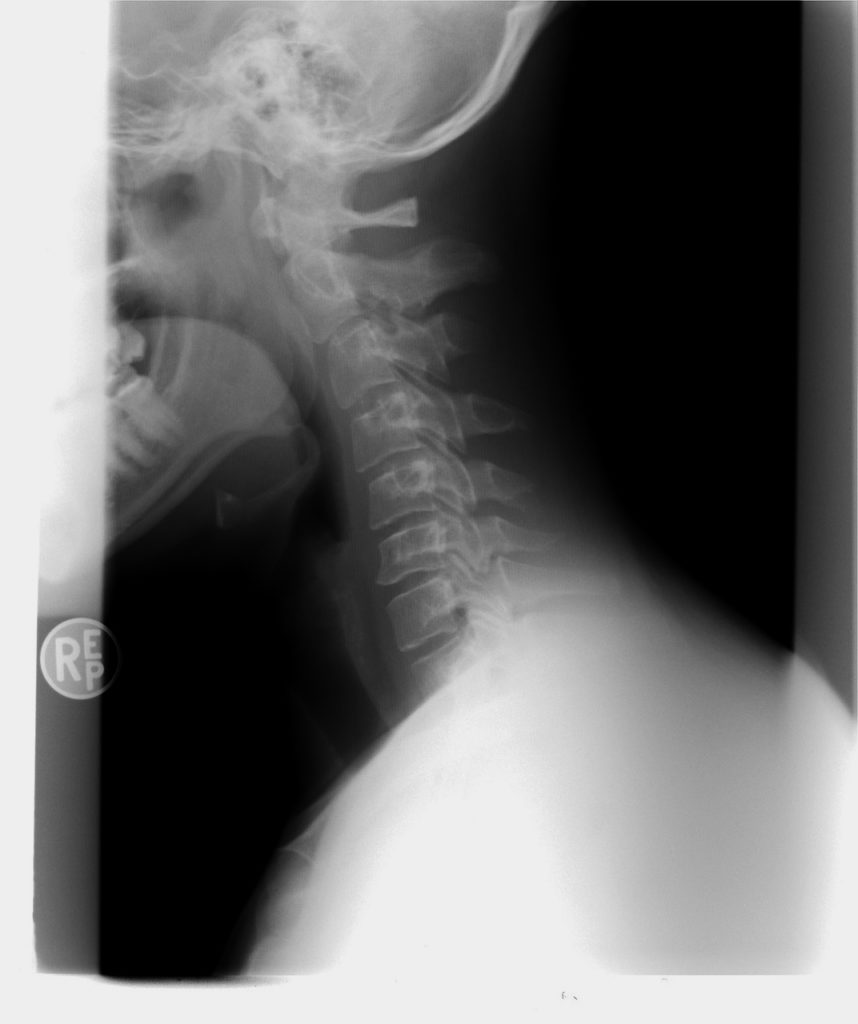

Headaches can come from many causes, and one common problem is our posture. We do so many things in front of us and down – using the computer, phones, driving, etc. The normal C-shaped curve in the neck (called cervical lordosis) slowly decreases and can even start to curve in the opposite direction!